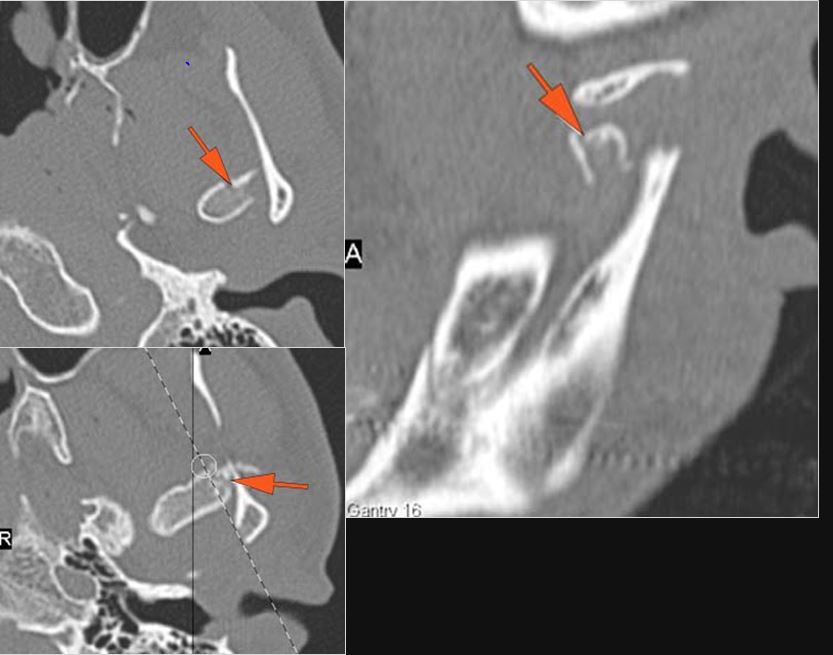

Right Temporal Bone

The roof of the mastoid and/or middle ear is fractured.

The ossicles, in particular the incus long process, the incudostapedial joint and stapes are fractured or dislocated.

The facial canal including the labyrinthine, tympanic and descending portions and nerve are fractured.

The inner ear including the lateral semicircular canals, vestibule and/or cochlea is fractured or otherwise abnormal.

Left Temporal Bone